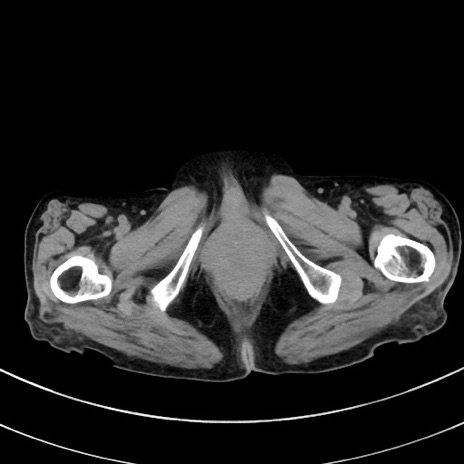

症例33(横断像)

【症例】70歳代 女性

【主訴】心窩部痛

【現病歴】延髄病変の精査・加療にて神経内科入院中。本日より心窩部痛あり。

【身体所見】右下腹部を中心に圧痛と反跳痛あり。

【データ】WBC 10900、CRP 0.02